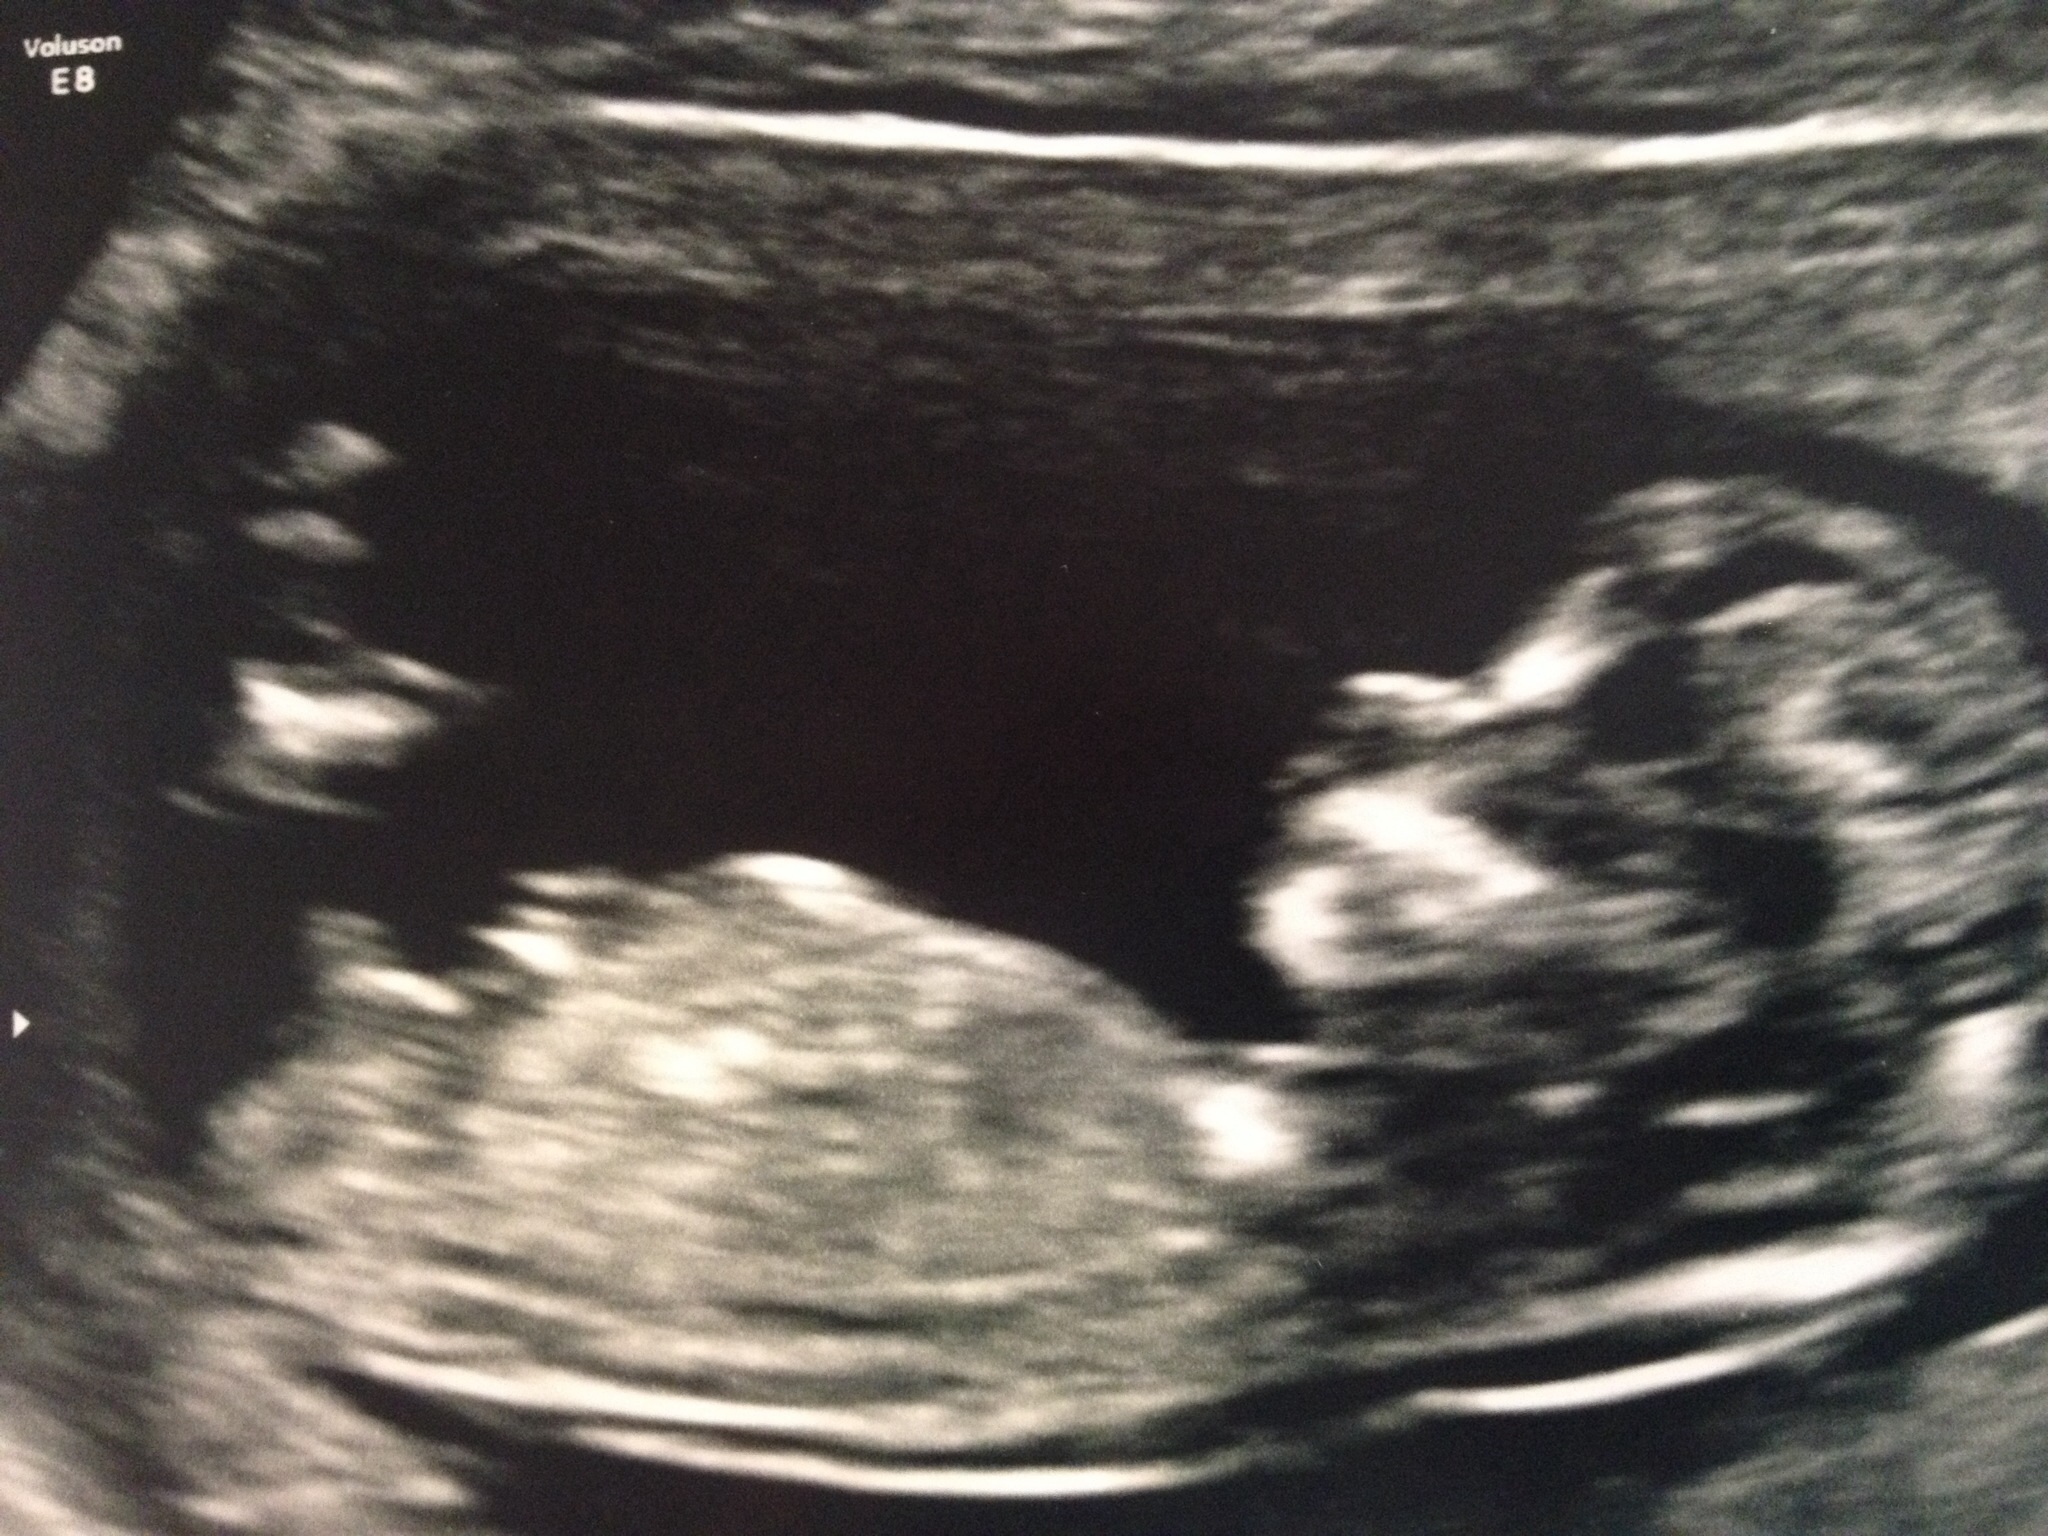

honest....so this is our last pregnancy. We have 2 boys and I'm not going to lie, both DH and I were hoping for a girl. I found a sonogram picture from last week with a pretty good view of the angle of the dangle. I posted it on www.in-gender.com and everyone is saying boy. Of course we are going to love and adore this baby but I'm feeling a little....not bummed I don't know the word. I was having visions of American girl dolls, sparkly clothes and getting our nails done together and it just doesn't look like that's going to happen for me. I'm not devastated or anything but I am wondering how accurate the angle of the dangle is? I'm attaching the picture.

I know exactly how you feel. Except I want another girl. If it's a boy, I will be disappointed but I know once the baby is here I won't care and will love him or her with all my heart. There was a post yesterday about the angle and it said straight was girl and 30 degree angle is boy. It looks like a girl to me!!

• sonographer mom also believes this looks to be a boy. she doesn't give 100% certainty with any of her thoughts though at this stage, so there's always room for change.

• @kristy774 I'm honestly so confused about this whole angle of the dangle theory.  Clearly, I am not the person to ask because I think it looks like a girly angle.  haha :-)